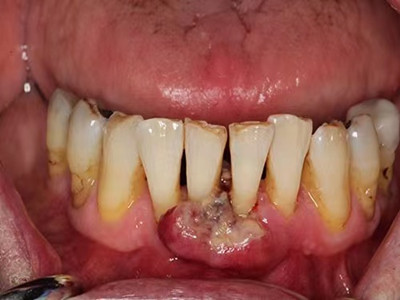

牙龈癌在口腔癌中仅次于舌癌而居第2位,组织学类型绝大多数为分化程度较高的鳞状细胞癌。牙龈癌好发于前磨牙区及磨牙区,下牙龈癌较上牙龈癌为多见,上下之比为2:1。牙龈癌发病年龄多为40-60岁,男性多于女性。

牙龈癌多源于牙间乳头及龈缘区,溃疡呈表浅、淡红,以后可出现增生。由于黏骨膜与牙槽突附着甚紧,较易早期侵犯牙槽突骨膜及骨质,进而出现牙松动,并可发生脱落。X线片可出现恶性肿瘤的破坏特征虫蚀状不规则吸收。

牙龈癌常发生继发感染,肿瘤伴以坏死组织,触之易出血。体积过大时可出现面部肿胀,浸润皮肤。